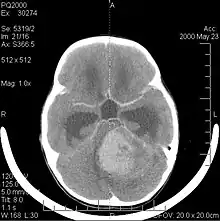

La tomodensitométrie (TDM) et L'imagerie par résonance magnétique (IRM) peuvent détecter efficacement une néoplasie dans le cerveau. L'IRM est plus sensible que la TDM pour identifier les lésions, mais présente des contre- indications pour les patients porteurs de stimulateurs cardiaques, de prothèses incompatibles, de clips métalliques et contre-indications. La TDM reste la méthode de choix pour détecter les calcifications au sein des lésions ou les érosions osseuses de la calotte ou de base du crâne. L'utilisation d' agents de contraste, iodés dans le cas du scanner et paramagnétiques (gadolinium) dans le cas de l'IRM, permet l'acquisition d'informations sur la vascularisation et l'intégrité de la barrière hémato-encéphalique, une meilleure définition de la tumeur tumorale par rapport à l' œdème environnant et à la génération d' hypothèses sur le degré de malignité. L'examen radiologique permet également d'évaluer les effets mécaniques et les modifications importantes des structures cérébrales résultant de la tumeur, telles que l' hydrocéphalie et les hernies, dont les effets peuvent être fatals. Enfin, en préparation à la chirurgie, ce diagnostic peut être utilisé pour déterminer la localisation de la lésion ou l'infiltration de la tumeur dans des zones vitales du cerveau. À cette fin, l'IRM est plus efficace que la tomodensitométrie car elle peut fournir des images en trois dimensions.

Les outils d'imagerie radiologique diagnostique mettent en évidence la modification du tissu néoplasique par rapport au parenchyme cérébral normal (par le biais de modifications de la densité tissulaire imagée électroniquement en TDM et de l'intensité du signal en IRM). Comme la plupart des tissus pathologiques, les tumeurs sont également reconnaissables par une accumulation accrue d'eau intracellulaire. Dans la tomodensitométrie, ils apparaissent hypodenses, c'est-à-dire de moindre densité que le parenchyme cérébral, dans la tomographie par résonance magnétique nucléaire avec relaxation spin-réseau hypointense et en relaxation spin-spin ainsi que l' hypersignal en pondération protonique (PD).

La tomodensitométrie du cerveau montre généralement une masse tissulaire qui peut être améliorée par l'un ou l'autre contraste. Au scanner, les gliomes de bas grade apparaissent généralement isodenses au parenchyme normal et peuvent donc ne pas présenter de rehaussement de contraste. De même, les lésions de la fosse crânienne postérieure sont difficiles à identifier au scanner. Par conséquent, les seuls résultats d'une telle tomographie ne sont pas toujours suffisants à des fins diagnostiques. Dans les cas douteux, l'utilisation de l'imagerie par résonance magnétique plus sensible est indispensable.

Sur-L'IRM montre une tumeur intracrânienne comme une lésion massive qui peut devenir plus luminescente après utilisation du produit de contraste. Cependant, il y a toujours une anomalie de signal dans -L'imagerie par résonance magnétique, qui indique la présence d'une néoplasie ou d'un œdème vasogénique. Habituellement, une luminescence accrue (amélioration du contraste) indique une tumeur d'un grade supérieur de malignité. Un anneau de contraste est caractéristique du glioblastome, avec la partie luminescente correspondant à la partie vitale de la tumeur maligne, et la plus foncée - zone hypointense correspondant à une nécrose tissulaire.

Les métastases cérébrales sont les néoplasmes intracrâniens les plus courants chez les adultes, étant dix fois plus fréquents que les tumeurs cérébrales primaires. Ils marchent à 20 jusqu'à 40 pour cent des adultes atteints de cancer et sont principalement associés au cancer du poumon et du sein et au mélanome . Ces lésions résultent de la propagation des cellules cancéreuses dans la circulation sanguine et surviennent le plus souvent à la jonction de la matière grise et blanche, où la section transversale des vaisseaux sanguins change, emprisonnant les embolies de cellules tumorales . 80 % des lésions surviennent dans les hémisphères cérébraux, 15 pour cent dans le cervelet et 5 pour cent dans le tronc cérébral. Environ 80 % des patients ont des antécédents de cancer systémique et 70 pour cent ont de multiples métastases cérébrales.

Des progrès significatifs ont récemment été réalisés dans le diagnostic et le traitement de ces lésions, entraînant une amélioration de la survie et du contrôle des symptômes. L'apparition des signes et des symptômes est similaire à celle d'autres lésions massives du cerveau. La méthode de diagnostic de choix est l'imagerie par résonance magnétique utilisant des produits de contraste.